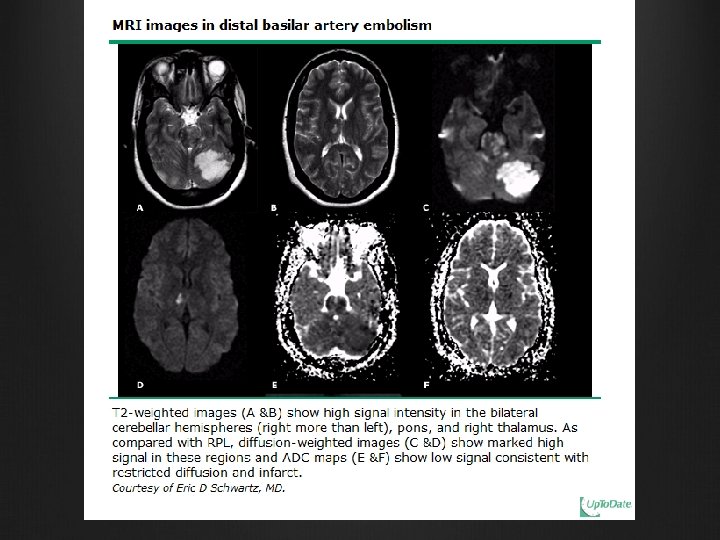

Neurological imaging MRI Much more effective than CT T 2 hyperintense signals at parieto-occipital and temporal lobes, occasional involvement of basal ganglia and/or brainstem ‘New’ MRI techniques for better characterization / differentiating from other causes E. g. diffusion weighted imaging and apparent diffusion coefficient mapping (ADC) Neurological complications of pre-eclampsia GG. Zeeman Seminars in perinatology 2009; 33: 166 -172

Neurological The posterior circulation is particularly vulnerable because of less sympathetic innervation and lower ability to respond to elevated blood pressure Maybe complicated with intracranial haemorrhages / cerebral infarction Most common clinical manifestations Headache Seizures Visual disturbance Altered mental state Neurological complications of pre-eclampsia GG. Zeeman Seminars in perinatology 2009; 33: 166 -172

Neurological imaging CT scan Localized hypodense lesions at gray white matter junction in parieto-occipital lobes. Less commonly in frontal, inferior temporal lobes, basal ganglia and thalamus Intracranial haemorrhages usually at the striatocapsular area, thalamus, cerebellum and brain stem Neurological complications of pre-eclampsia GG. Zeeman Seminars in perinatology 2009; 33: 166 -172